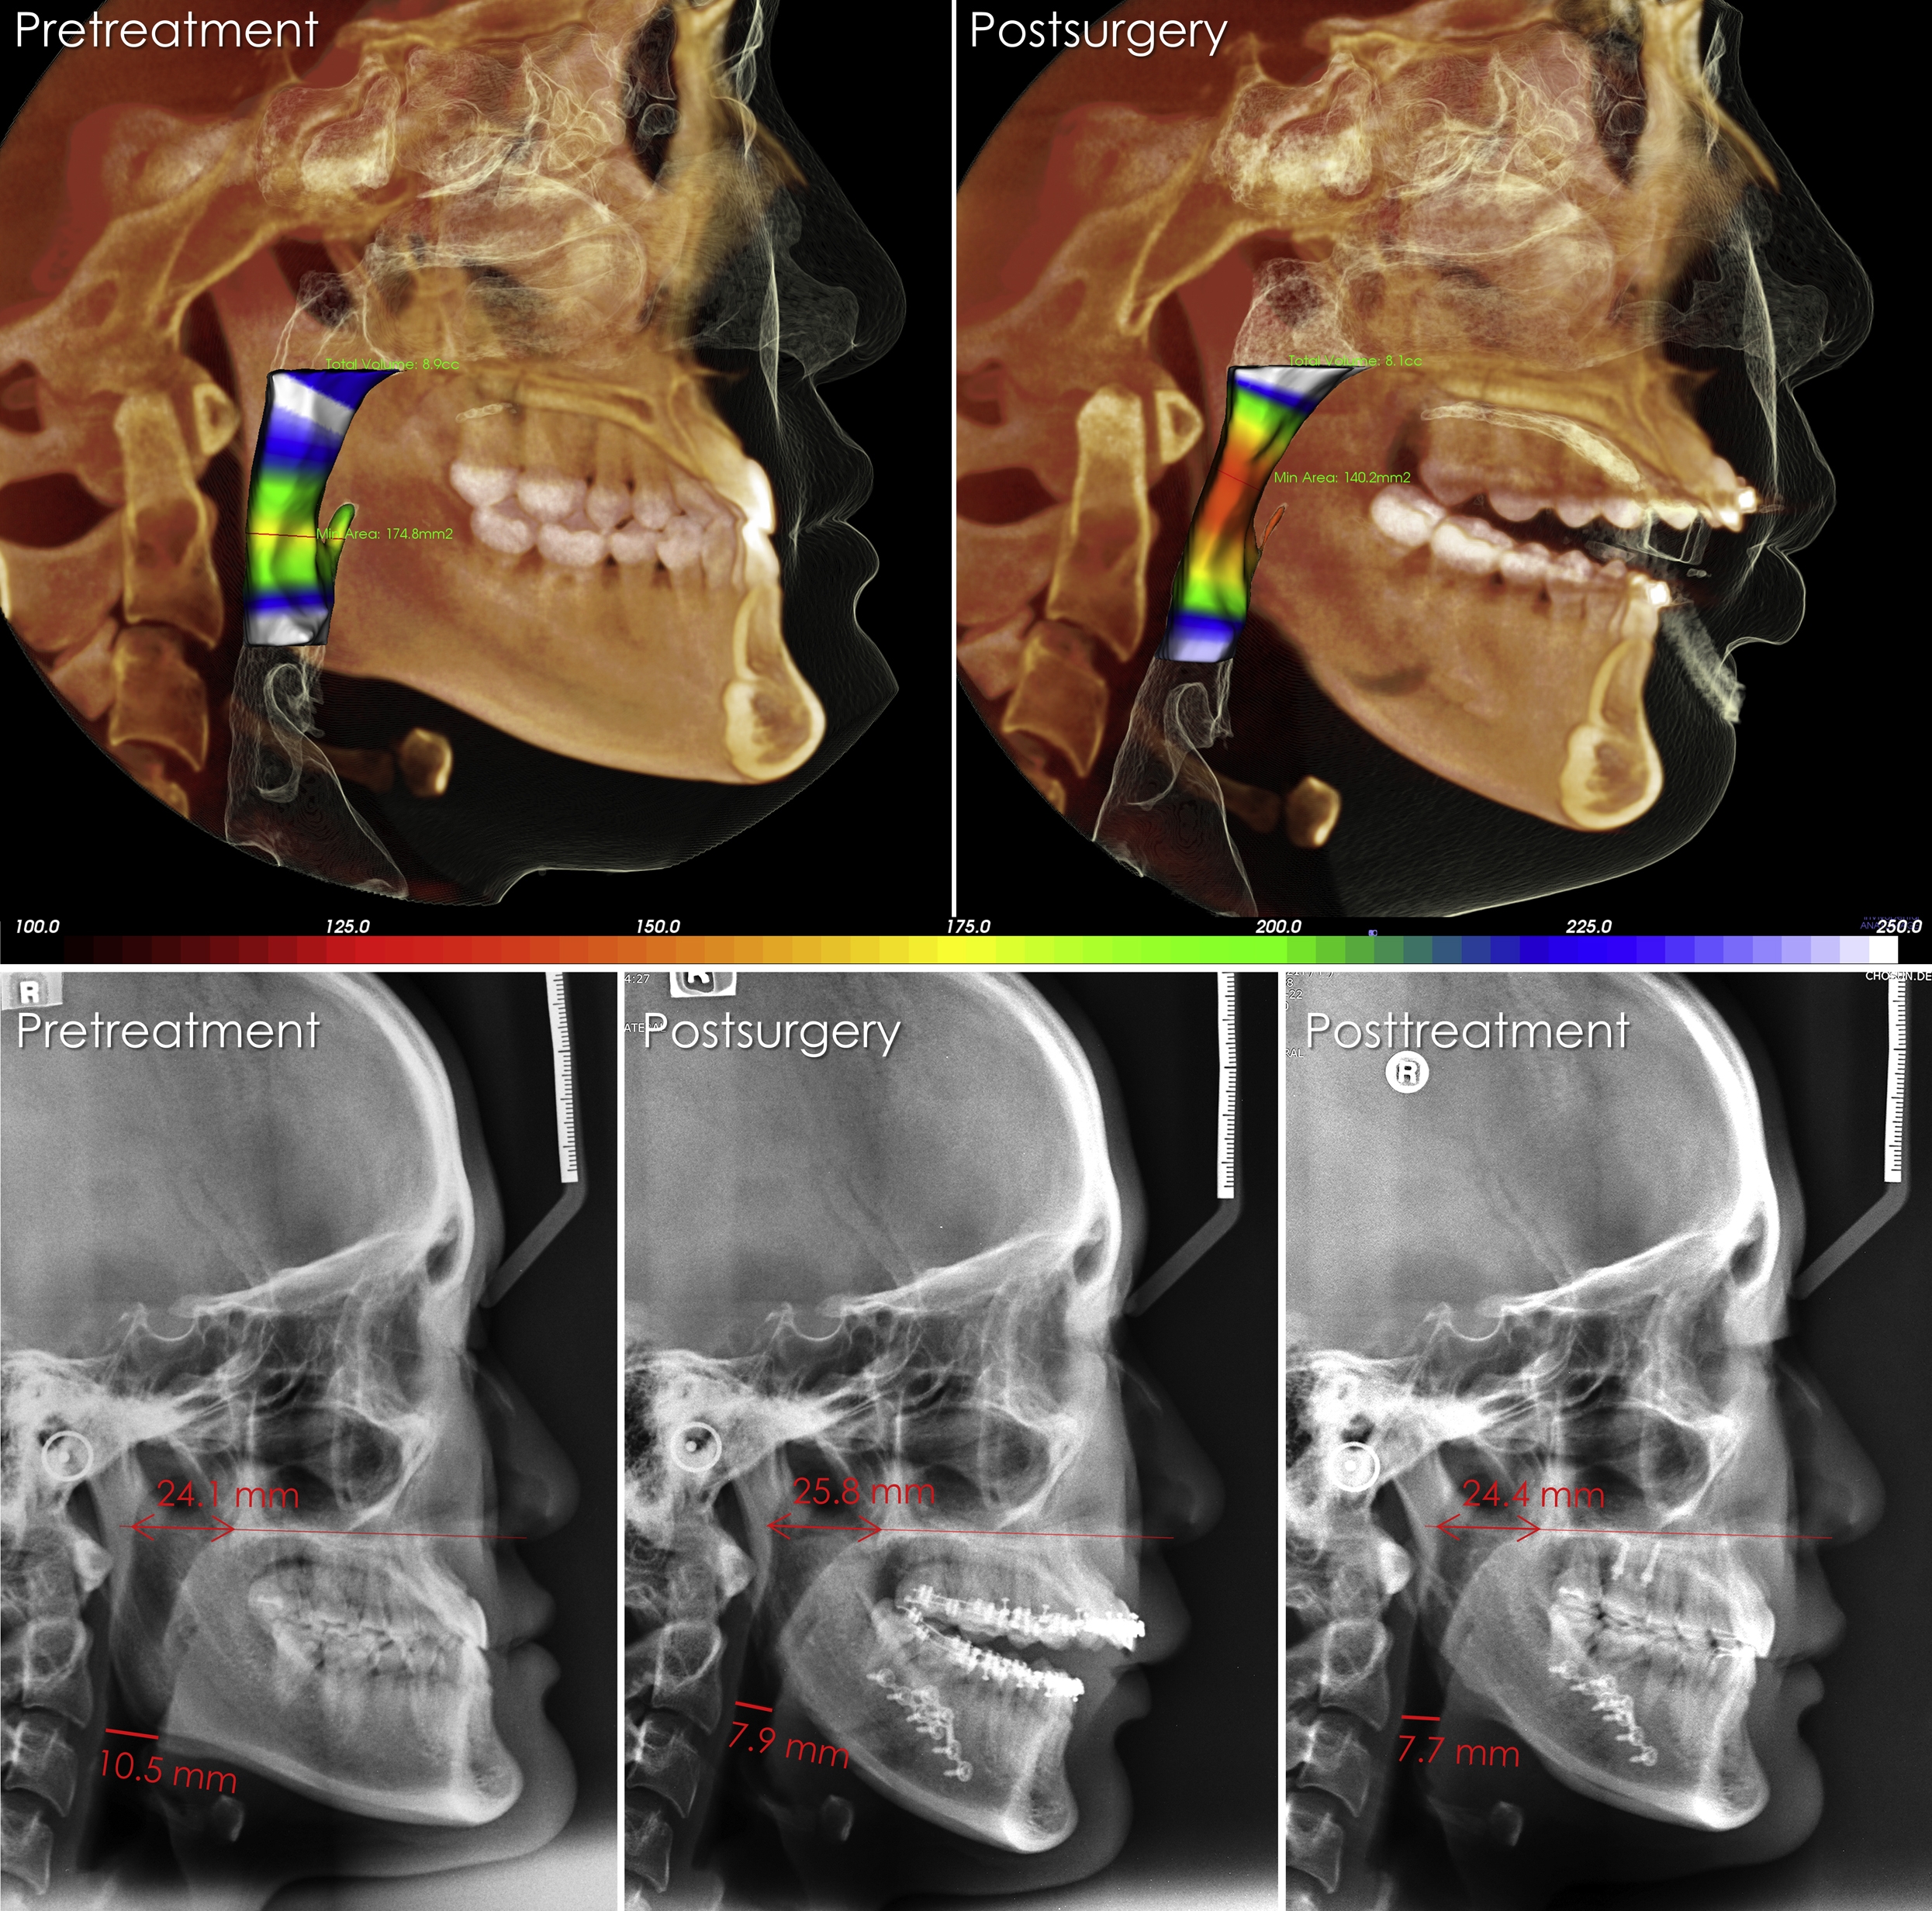

Нижнечелюстной прогнатизм

Нижнечелюстной прогнатизм 113 фото